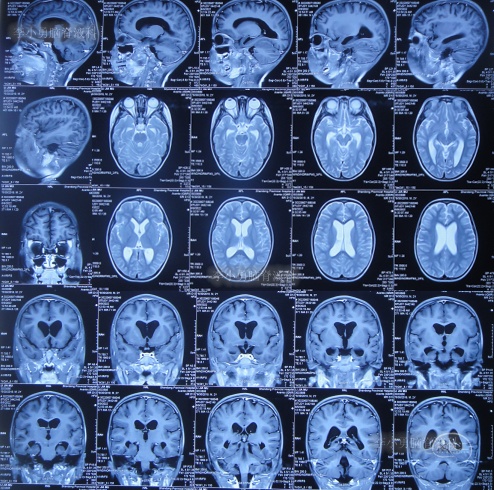

住院治疗7天即2022年5月18日,出现头痛,呕吐,体温再次升高为39.6度,心电图示室性心动过速,室早,考虑“心肌炎”,查头颅核磁(图-1)后并行腰穿见脑脊液呈金黄色,留取脑脊液送常规化验提示诊断为颅内感染,给予抗感染治疗。

图-1:2022年5月18日头颅核磁

第3家医院治疗16天即2022年6月9日,不但依然发热,而且查头颅CT示脑室稍扩张(图-3)。

图-3:2022年6月9日头颅核磁

但该院治疗12天即2022年6月29日,复查头颅核磁脑室扩张进一步加重(图-6)。

图-6:2022年6月29日头颅核磁